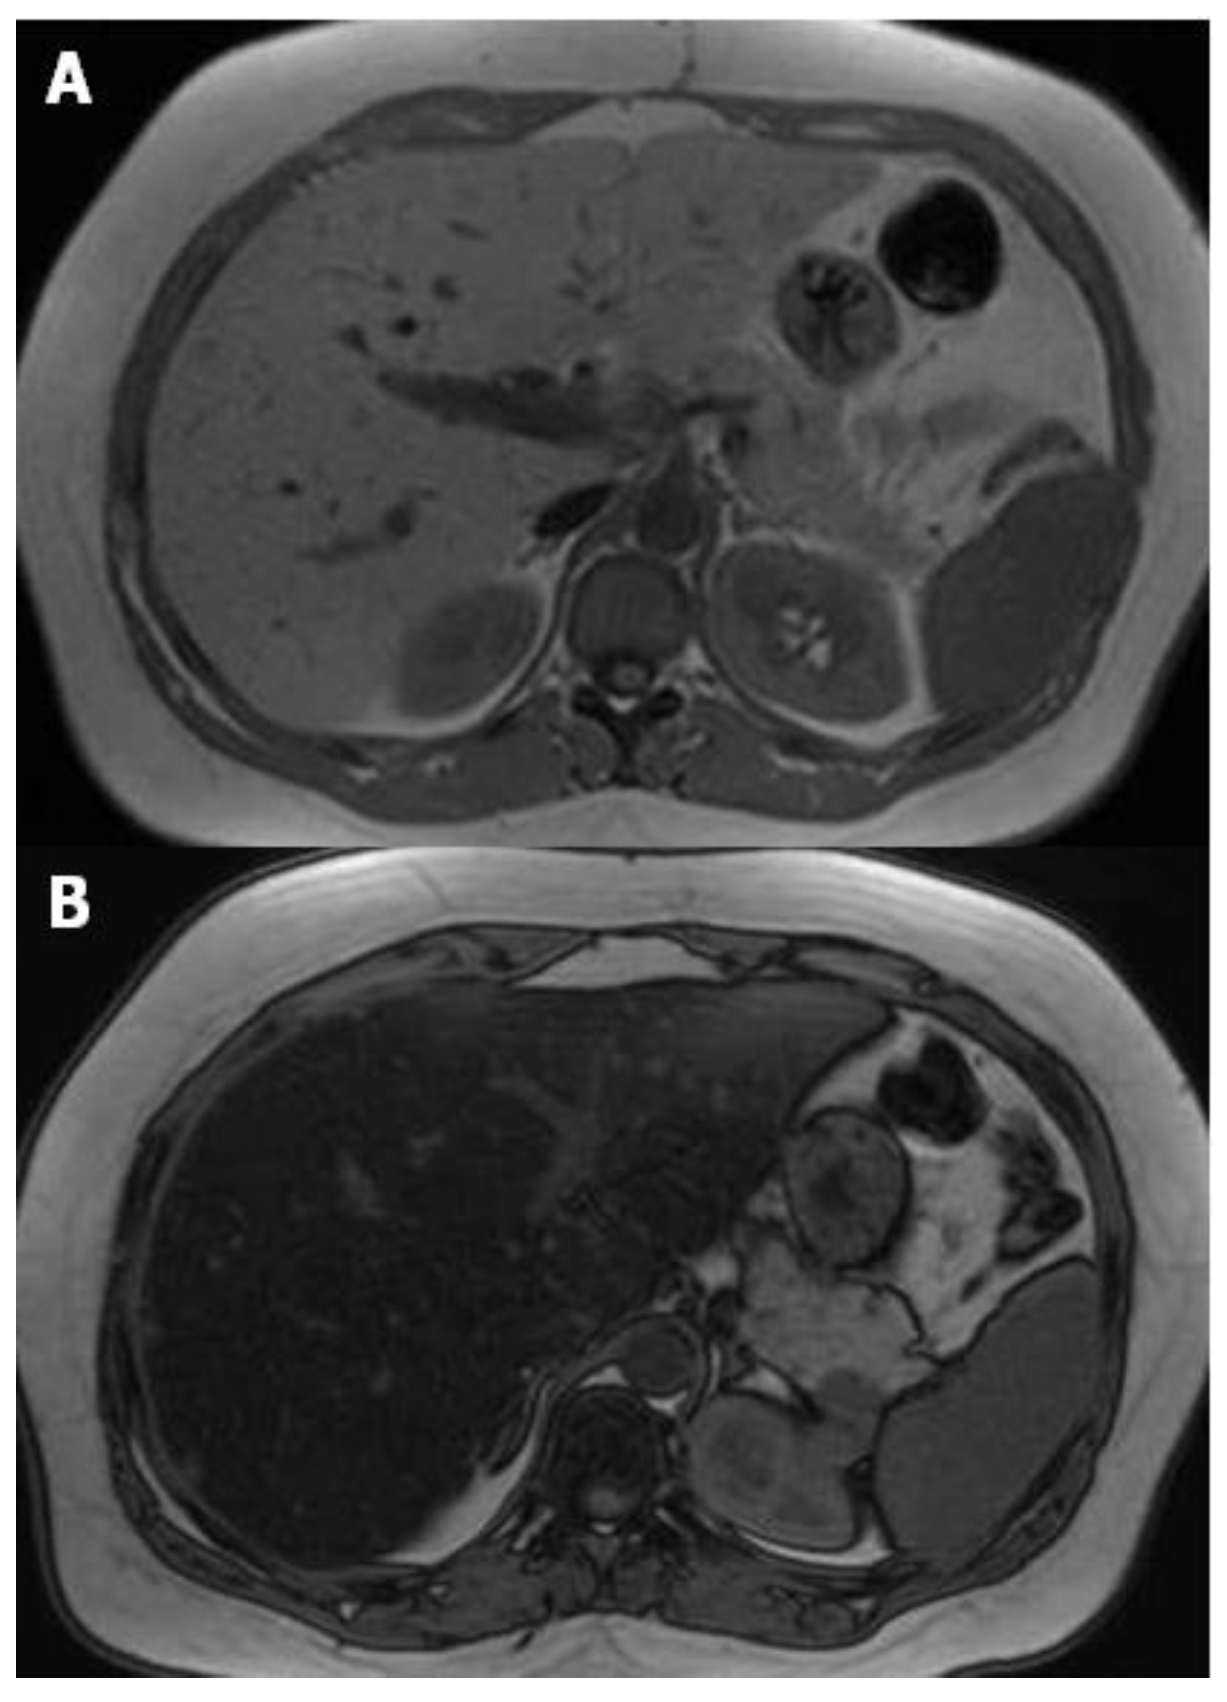

3. Magnetic Resonance